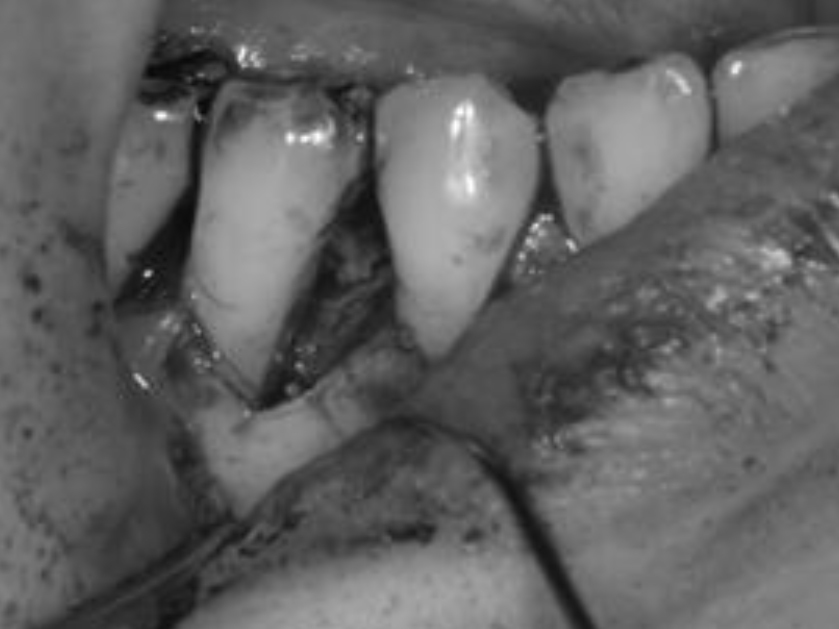

歯周基本治療・根管治療・歯周外科処置を行なった症例

初診時

歯周基本治療・

根管治療後

歯周外科処置

歯周外科処置後

初診時年齢:

治療:歯周病治療・う蝕治療

治療法:歯周基本治療、歯周外科治療、感染根管治療

治療期間:1年3ヶ月

費用:保険診療

リスク・副作用:歯周外科処置後に出血、腫れ、あざが出ることがありますが時間とともに治ります。術後3週間程度噛んだときの痛みや歯が浮いた感じがすることがあります。

感染根管処置中に腫れ、痛みが出ることがありますが時間とともに治ります。